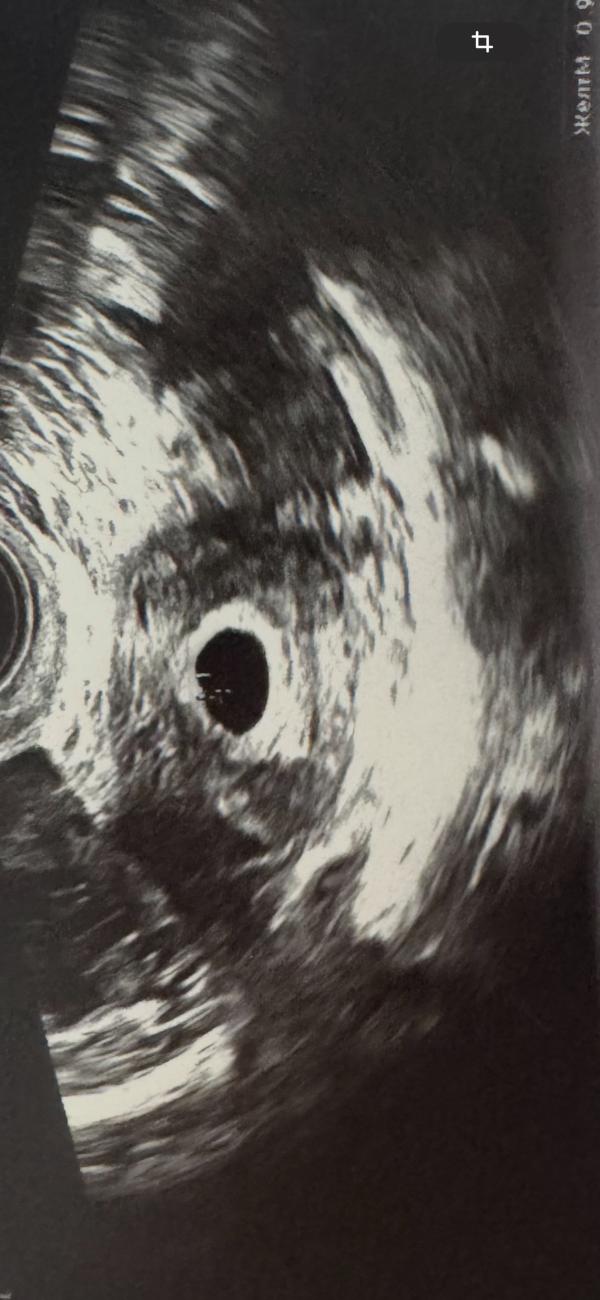

Сделали узи

Гематом нет

Отслоек тоже

Плодное яйцо ровное

Эмбриончик видно

Сказали все соответствует дате переноса

Сердцебиение можно прослеживать будет не раньше ,чем через 2 недели